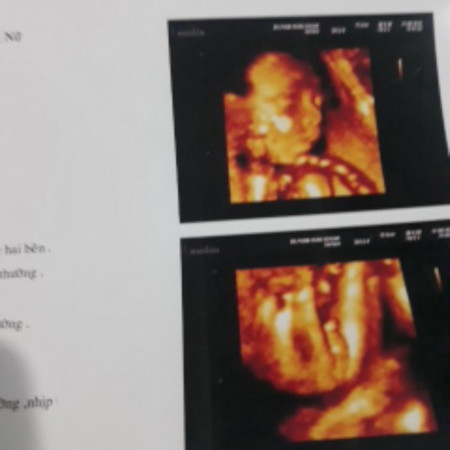

cu bin của ba mẹ nè iu con .

cubin iu quá